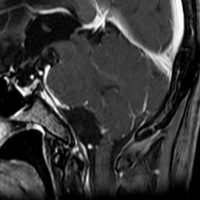

骨内髄膜腫 osseous meningioma

骨内増殖をする髄膜腫です。頭蓋骨腫瘍と間違えるようなものです。触った感じは骨腫ですが,CTでは,表面が毛羽立っていて,頭蓋冠に浸潤していることが特徴です。浅側頭動脈からの豊富な血流があります。

わずかですが頭蓋内にも腫瘍があり,硬膜が肥厚してガドリニウム増強されます。

頭蓋骨をかなり広範におかすので骨は捨てません。開頭して取り外した骨の厚くなっている部分と髄膜腫で軟らかくなっている部分を削除して,それから骨片をオートクレーブで短時間熱処理して,元あった所にもどします。下の画像は手術後1年半が経過したものですが,髄膜腫の再発はなく,熱処理骨弁は吸収されないで生着しています。